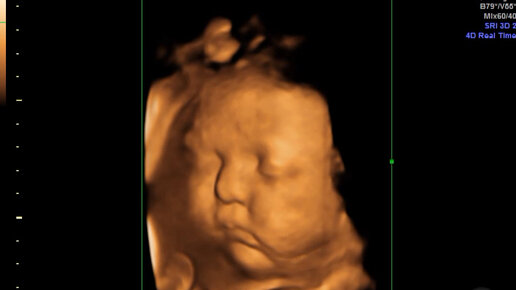

Что такое 2 скрининг? Зачем нужна процедура? И сколько показателей изучается? Все это волнует будущих мам.  Что входит в скрининг 2 триместра? Этапы II-го скрининга: Для проведения УЗ-диагностики подготовительные мероприятия не нужны. Биохимический анализ сдается натощак.  Когда проходит скрининг?  Сроки проведения второго скрининга при беременности следующие:  Помните, что только акушер-гинеколог на очной консультации может проводить расшифровку данных вашего обследования.  Результаты биохимического...

Второй скрининг в период вынашивания ребёнка — это специальный комплекс диагностических мероприятий. Его основная задача — выявление отклонений от нормы в развитии эмбриона. А также лабораторное исследование помогает подтвердить результаты первого скрининга. Процедура, как правило, платная, и в каждой клинике цена может значительно отличаться. Несмотря на то что скрининг стоит денег, для некоторых женщин его проведение во 2 триместре желательно и даже необходимо. В этот период ребёнок начинает активно развиваться в утробе матери, что может спровоцировать различные сбои в работе организма...